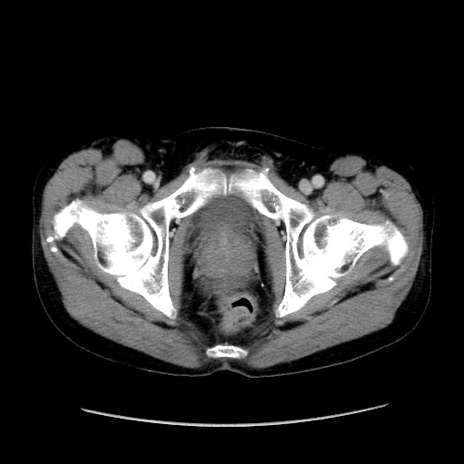

冠状断像